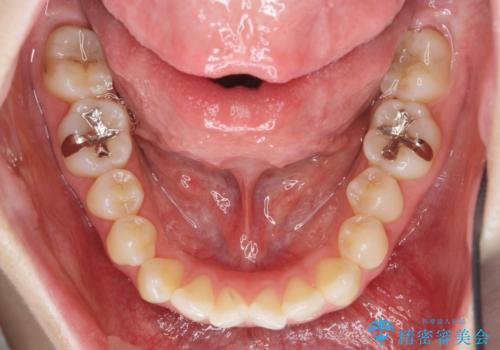

上下の歯は、上顎の歯が相対的に前に位置する咬合関係で押し出されるように前歯に角度がついている状態です。

咬合関係の改善、前歯の角度、がたつきを改善するため、マイクロインプラントを用いて上顎の奥歯を後方へ移動させていきます。